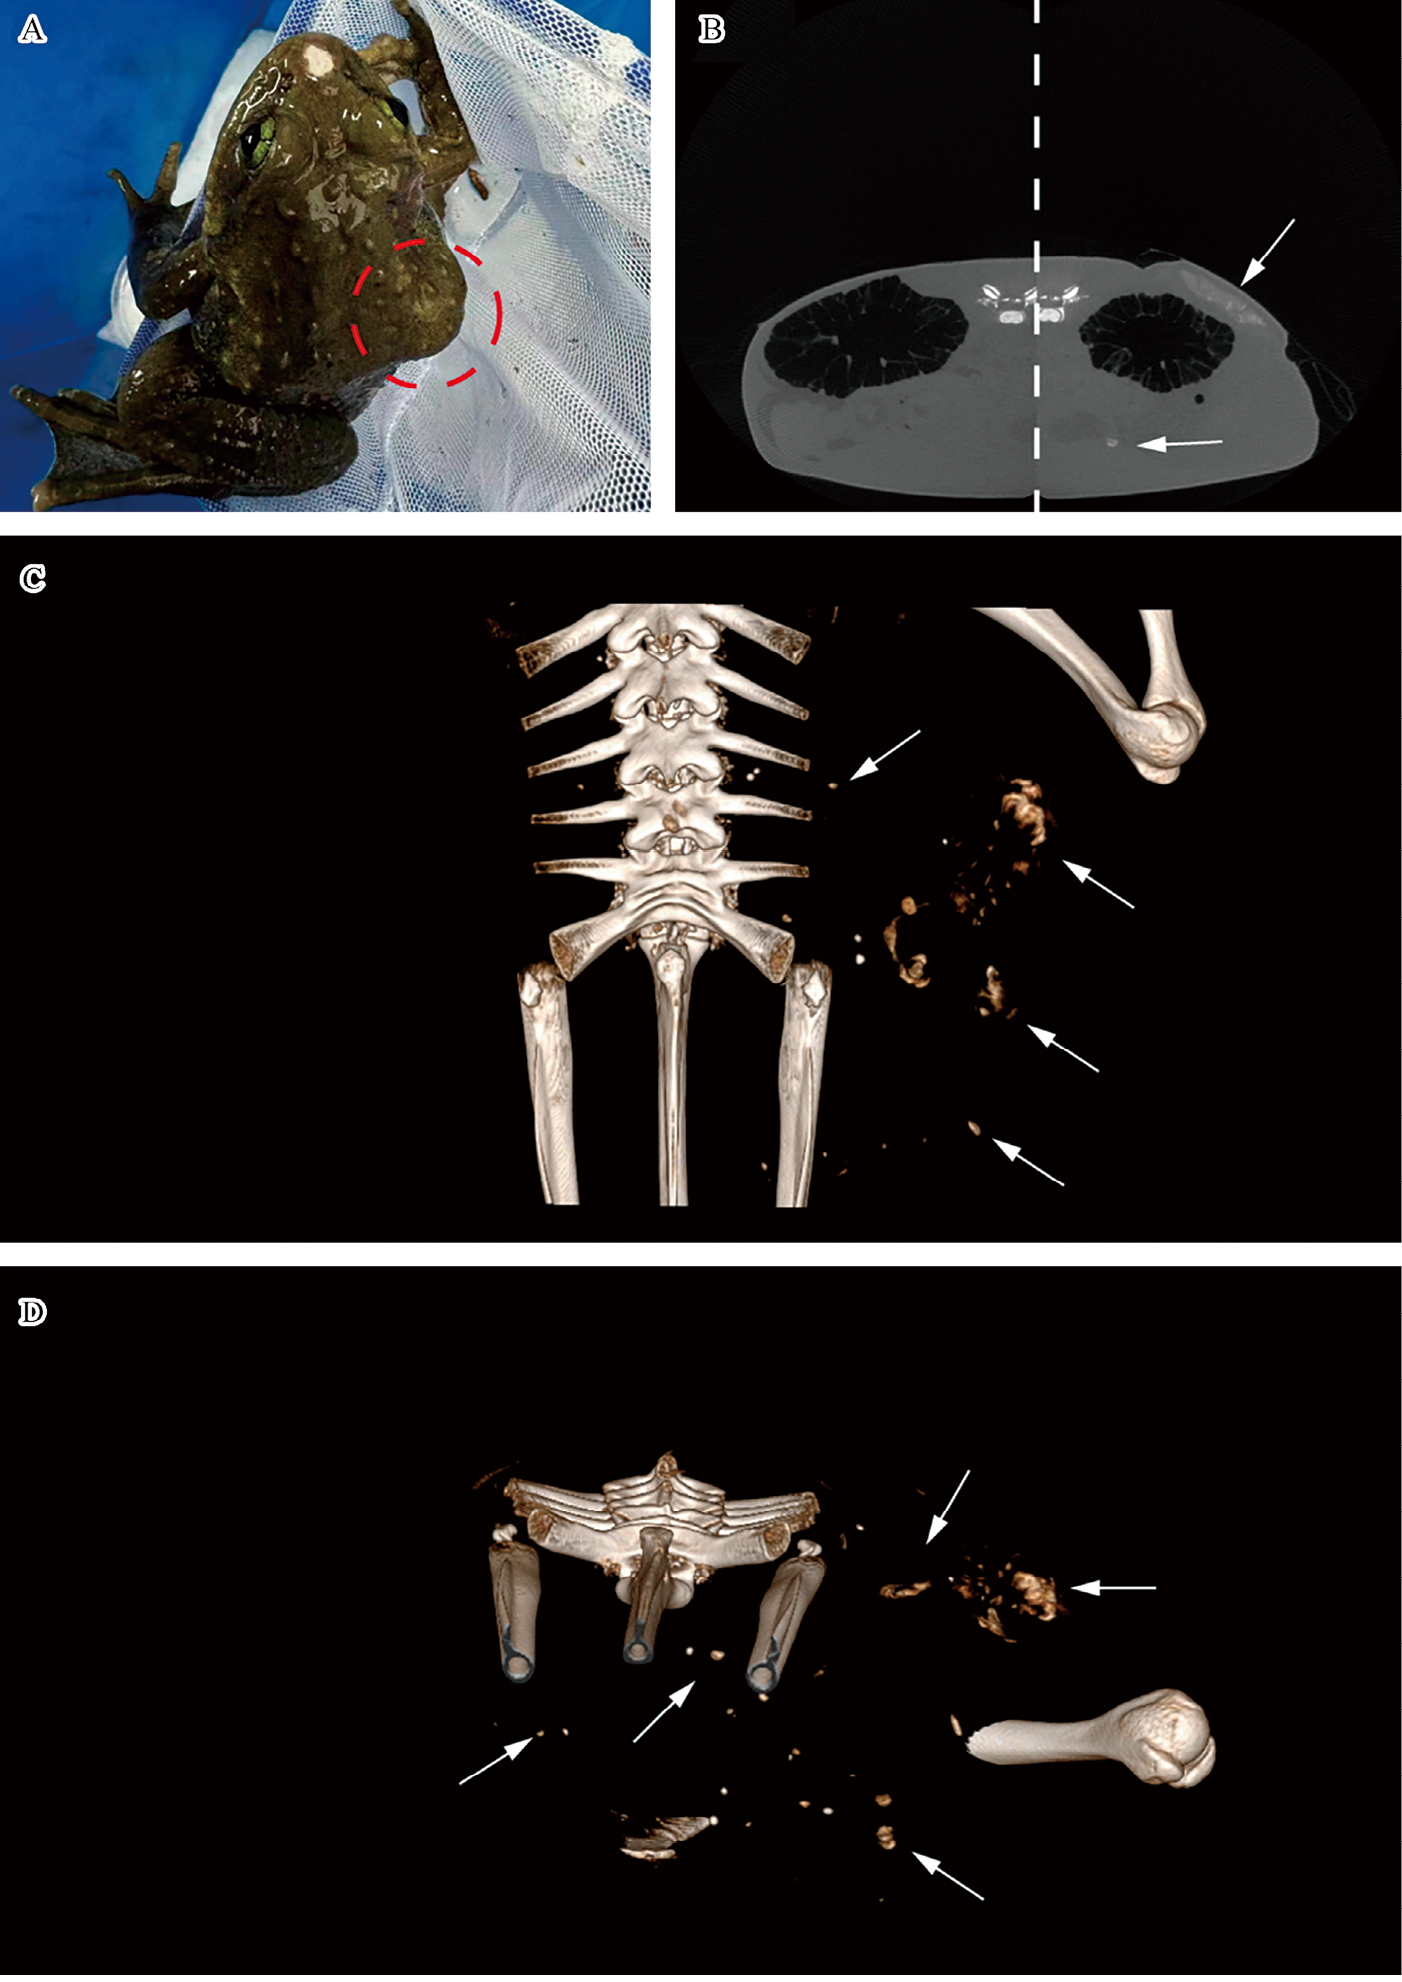

(5)首次记录了野生墨脱棘蛙的去分化脂肪肉瘤病例

去分化脂肪肉瘤(DDLPS)是一种罕见且极具侵袭性的癌症类型,起源于脂肪组织,此前仅在人类中有所记录。在该项研究中,首次记录了野生两栖动物物种墨脱棘蛙(Nanorana medogensis)中的DDLPS病例,并运用微计算机断层扫描(micro-CT)、组织学分析和免疫组织化学等先进的诊断技术,确认了这一诊断(图3-163)。作为环境变化的指示器,两栖动物为研究者提供了一个独特的视角,有助于理解生态系统的变化如何导致癌症等疾病的发生。另外,研究结果强调了在兽医病理学中采用综合诊断方法的重要性,并且为日益发展的野生动物健康研究领域做出了贡献,跨物种癌症研究不仅有助于提升兽医和人类医学的研究水平,还为癌症生物学和潜在治疗方法的研究提供了新的视角。2024年,该研究成果发表于期刊Veterinary Sciences

图3-163 DDLPS病例的病变组织形态及微计算机断层扫描结果